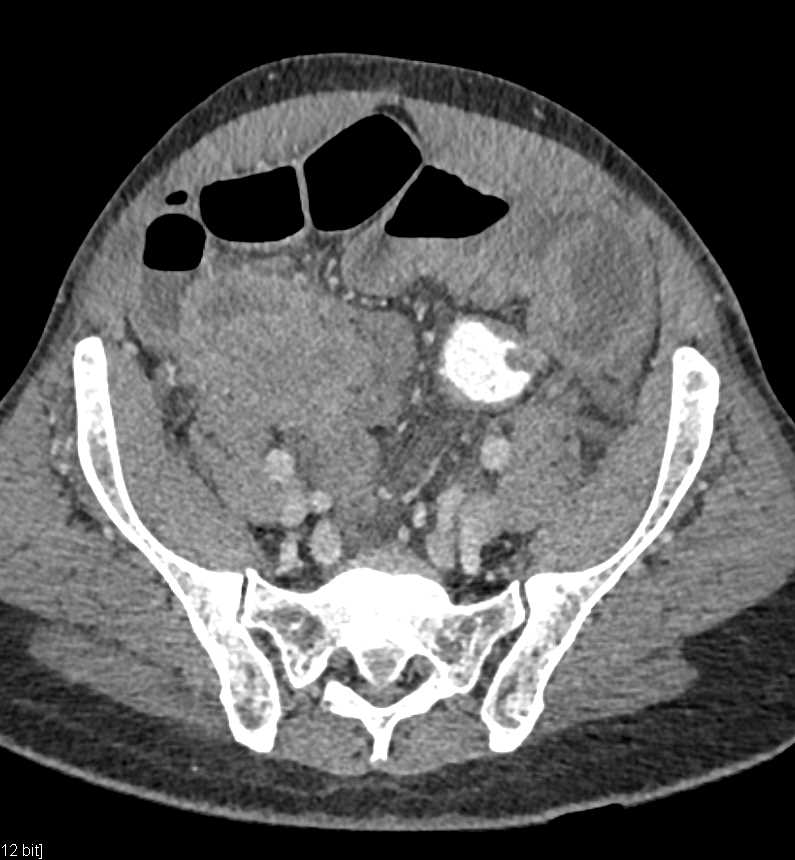

Small Bowel Carcinoma with Carcinomatosis